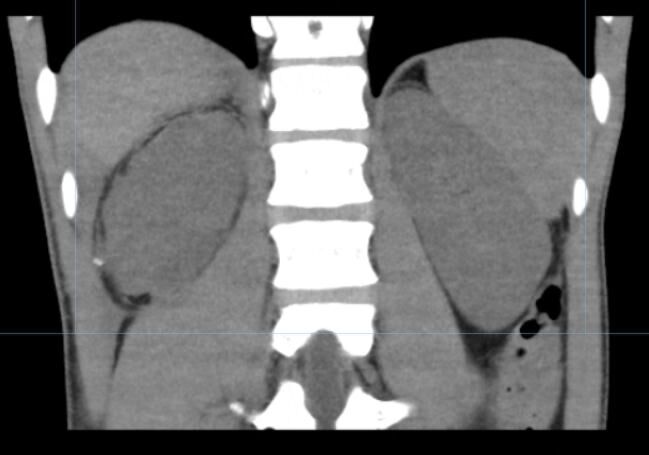

小叶在中山七院急诊进行了影像学检查,检查发现他的右肾下极碎裂,右肾多处裂伤,右肾周巨大血肿。经七院泌尿外科二值会诊后即刻转入泌尿外科病区。泌尿外科主任庞俊指示,密切观察小叶的生命体征、血常规、尿液颜色。庞俊主任带领科室骨干与麻醉科同事立刻进行了术前讨论,虽然小叶的右肾严重碎裂,术中大出血风险极高,保肾难度极大,但考虑到他年纪轻,医生们定下了尽可能保留肾脏的手术方案。

在七院手术麻醉中心的高效配合下,术前准备一切就绪。一场保肾的攻坚战打响了。此次手术行开放手术探查,庞俊主任主刀。术中探查正如CT图片所看到的那样,肾脏下极完全离断,肾门处也有两块碎裂肾组织,肾脏分裂为4部分。医生在开放进入腹膜后腔后物理降温(用冰水),在不打开肾周围筋膜情况下阻断肾蒂,阻断了肾脏的血供,避免肾周筋膜打开后引起大出血。为了避免时间太长组织可能会缺血坏死,这要求主刀医生必须在极其有限的时间内(热缺血时间尽可能不超过30min)清除血肿,缝合肾组织创缘。

小叶右肾术前CT图片